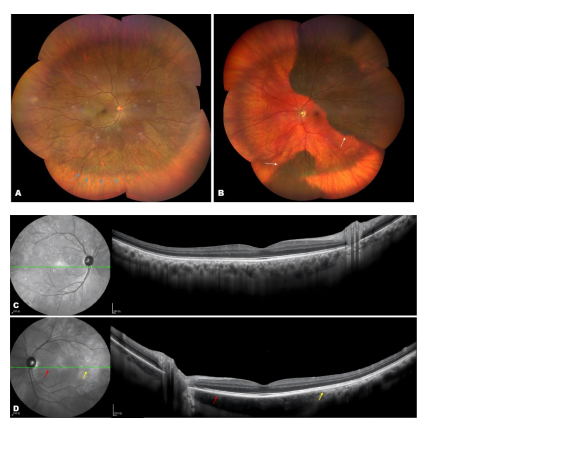

A 60-year-old man of Asian descent presented for regular medical examinations. His best corrected visual acuity was 20/25 OD and 20/25 OS. Slit-lamp examination revealed mild nuclear and cortical cataracts as well as slightly vitreous opacities. The anterior segments shown no other features of ocular melanocytosis. During funduscopic examination, bilateral choroidal melanocytosis with an asymmetry choroidal pigmentation changes was observed. In the right eye, there was diffuse darker coloration from posterior pole to the mid-peripheral retina (Fig 1-A). In the left eye, flat patches of choroidal hyperpigmentation were present, involving the  superior and inferior hemisphere regions, while other regions was depigmented (Fig1-B).The margin of hyperpigmentation area on the fundus were indicated by arrow heads in Figure 1.Spectral-domain optical coherence tomography (SD-OCT) revealed normal retinal layers with slightly increased choroidal thickening (Fig 1-C, D). There is no elevation of the retinal pigment epithelium (RPE) or any choroidal mass.Changes in choroidal pigmentation (either an increase or a decrease) led to alterations in OCT findings. Figure 1-D clearly shown an indistinct Sattler’s layer and Haller’s layer at the area of hypopigmentation (red arrow ) and slightly thickened choroid with a distinct structure in the area of hyperpigmentation(yellow arrow).Near infrared reflectance (NIR) images provide a clearer view of mottled focal hyperpigmentation corresponding to the choroidal hyperpigmentation (Fig 1-C, D). The patient denied any ocular history, especially past episodes of uveitis. Additionally,  the patient had no other systemic diseases, including dermatological disease such as vitiligo. After a physical examination, no other skin melanocytosis, cutaneous hypopigmentation, or white forelock was found. Based on the medical history, systemic examination, and fundus multimodal imaging, the patient was diagnosed with choroidal melanocytosis with asymmetric fundus manifestations. Although choroidal melanocytosis is typically benign, several studies have identified a potential association between choroidal melanocytosis and choroidal melanoma[4,6-7]. Therefore, the patients requires lifelong follow-up.

Figure 1 Multimodal imaging demonstrated bilateral choroidal melanocytosis with asymmetric pigmentation patterns

On wide-field fundus photography, the right eye displays diffuse posterior-to-midperipheral choroidal hyperpigmentation (A, indicated by the blue arrowhead), while the left eye shows patchy hyperpigmentation in the superior hemisphere and inferior midzone (B, indicated by the white arrowhead). Near-infrared reflectance imaging reveals slight mottled focal hyperreflective area in the right eye (C) and patchy hyperreflective area with clear border in the left eye that corresponds to the choroidal hyperpigmentation (D). The SD-OCT findings for both eyes show no elevation of the RPE or choroid. Figure D clearly illustrates the indistinct Sattlers layer and Haller’s layer in the area of hypopigmentation (red arrow), along with slight thickening of the choroid and well-defined choroidal structure in the area of hyperpigmentation (yellow arrow).